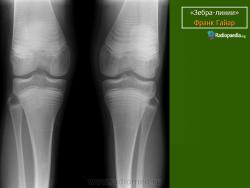

Рентгенологические изменения зависят от тяжести патологического процесса. Основным признаком является распространенный остеопороз всего скелета. Окружающие срастающийся перелом периостальные мозоли иногда достигают огромных размеров, симулируя опухоль (псевдосаркома). Отмечаются резкое истончение кортикального слоя, уменьшение диаметра кости. Характерна платиспондилия различной степени; позвонки приобретают двояковогнутую форму. Черепные швы расширены, с большим количеством непостоянных так называемых вормиевых косточек.

Рентгенологически. Выражен остеопороз костей, истончение кортикального слоя, следы множественных переломов и избыточного мозолеобразования, укорочение костей, сколиоз или кифосколиоз.